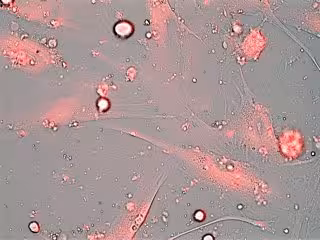

Los investigadores han evaluado la utilidad de los nuevos nanodispositivos en cultivos celulares primarios derivados de pacientes con el síndrome de envejecimiento acelerado Disqueratosis Congénita (DC). Dichos cultivos presentan un alto porcentaje de senescencia, caracterizada por elevados niveles de actividad de betagalactosidasa, una enzima característica del estado senescente. "Las células envejecidas sobreexpresan esta enzima; las nanopartículas que hemos diseñado se abren ante su presencia, liberando su contenido para eliminar las células senescentes, prevenir su deterioro o incluso reactivarlas para su rejuvenecimiento", apunta Murguía.